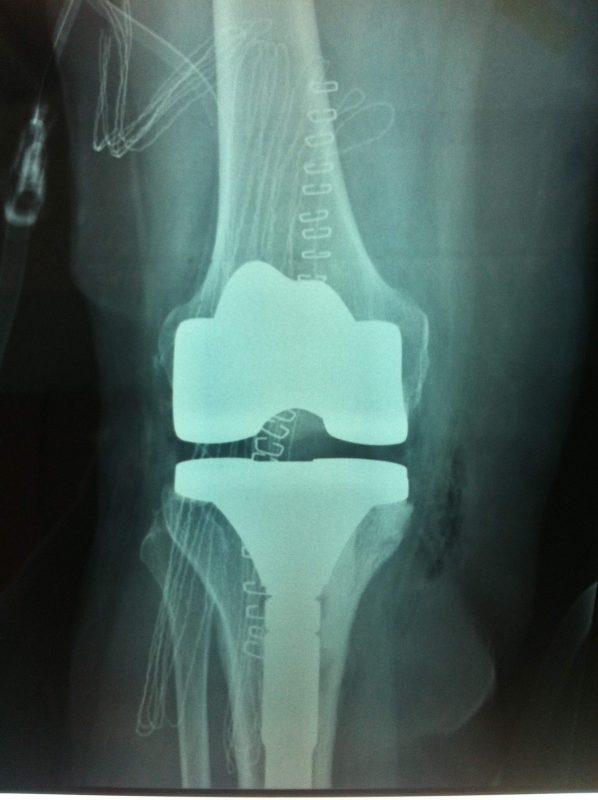

Παρόλα αυτά στην πλειονότητα των περιπτώσεων, με την πάροδο του χρόνου οι παραπάνω τρόποι αντιμετώπισης καθίστανται αναποτελεσματικοί. Η ένταση του πόνου και ο αντίκτυπος στην καθημερινότητα γίνονται αφόρητα.

Σε αυτό το σημείο η Αρθροπλαστική Γονάτου αποτελεί μονόδρομο.